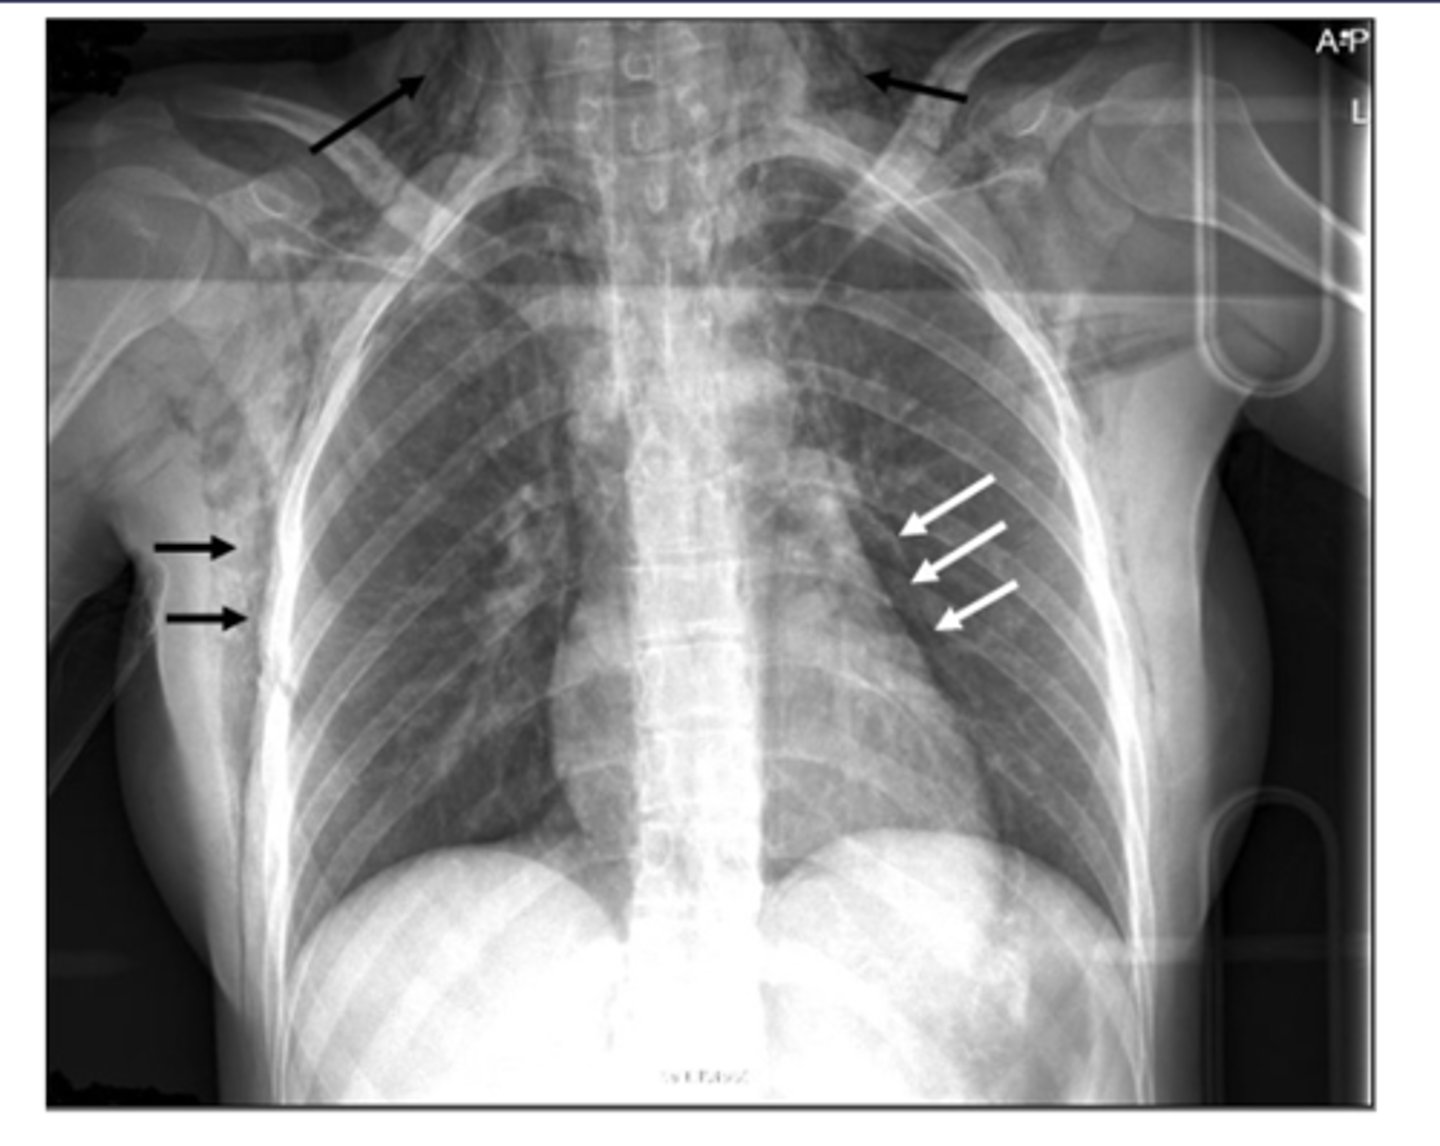

Black arrows: subcutaneous emphysema. White arrows: pneumomediastinum

ID black and white arrows

<p>ID black and white arrows</p>